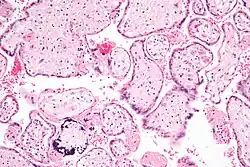

| CMV infection of a human lung pneumocyte | |

CMV infection can be demonstrated microscopically by the detection of intranuclear inclusion bodies. On H&E staining, the inclusion bodies stain dark pink and are called "owl's eye" inclusion bodies.[48]